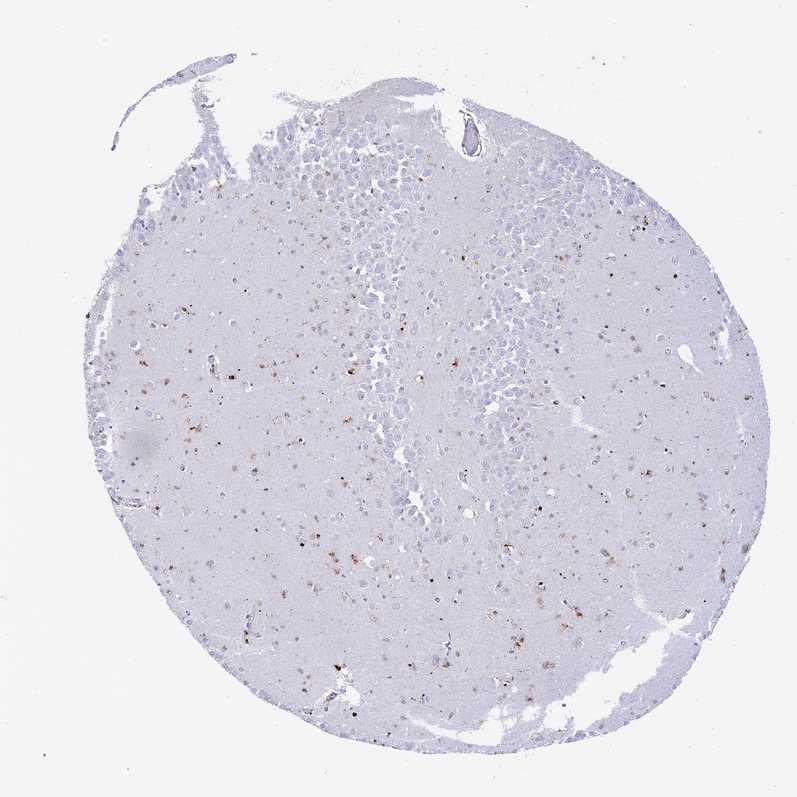

TISSUE PRIMARY DATA HIPPOCAMPUS Show tissue menu

HIPPOCAMPUS - Antibody stainingi

Antibody staining in the annotated cell types in the current human tissue is reported as not detected, low, medium, or high, based on conventional immunohistochemistry profiling in selected tissues. This score is based on the combination of the staining intensity and fraction of stained cells.

Each image is clickable and will lead to virtual microscopy that enables deeper exploration of all samples and also displays staining intensity scores, fraction scores and subcellular localization as well as patient and tissue information for each sample.

Antibody HPA042014Antibody HPA042844

Glial cells MediumNot detected

Neuronal cells LowLow